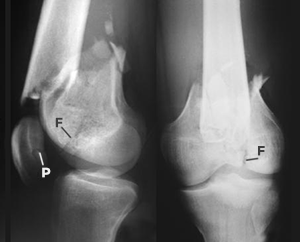

Hier das Röntgenbild einer schweren Knochenverletzung des Kniegelenkes. Der Bruch des Oberschenkelschaftes fällt sofort ins Auge. Weniger offensichtlich sind die Brüche an der Kniescheibe [Patella] (P) und an den Oberschenkelroffen [Femurkondylen] (F). Solche Haarrisse [Fissuren] können leicht übersehen werden.